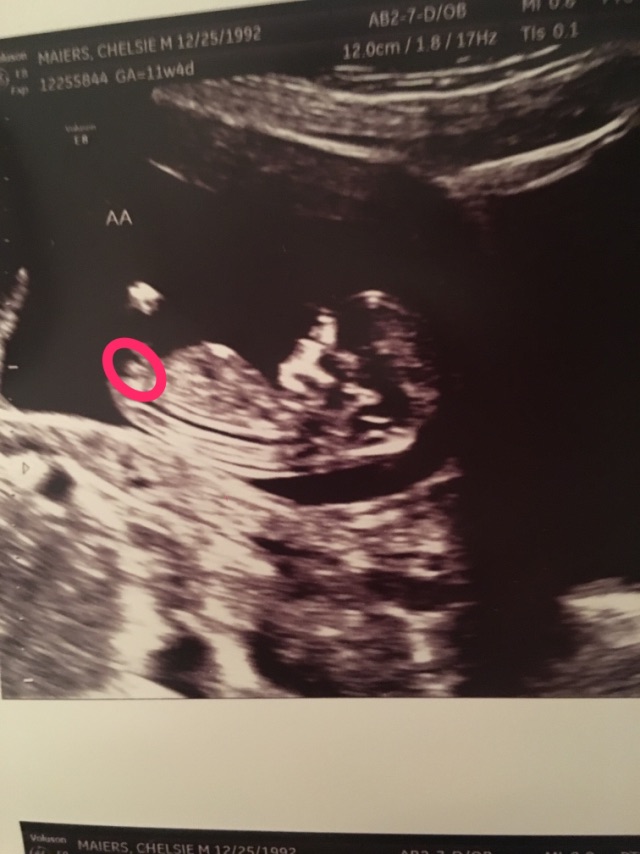

What Is A Gender Nub. Web the nub (genital tubercle) is your baby's developing genitals, so no theory over here. It can develop into a penis for males or a clitoris for females. It is supposedly the earliest point of prediction using modern technology; Luke’s hospital of southcoast hospitals in massachusetts. Web it’s the name given to a popular way of predicting your baby's sex, based on how their genitals (their ‘nub’) look on an ultrasound scan in your first trimester. All babies have this between their legs. All nubs will image as a fork. This fork is split into two parts. When is nub theory used? Web the gentical tubercle—or the “nub”—is the anatomical body part that exists between the legs of fetuses prior to 14 weeks, explains christian pope, do, facog, cheif of obstetrics and gynecology at st. Before 15 weeks of pregnancy, the baby is no bigger than a small chocolate bar. Web nub theory, on the other hand, provides an accurate gender prediction in roughly 9 out of 10 cases. So even if you’re still wondering, “what’s a nub in the first place?” our. Web what is nub theory? Web the ‘nub theory’ suggests it’s possible to tell the gender of your child in an ultrasound scan from as early as 12 weeks.

During the first part of pregnancy, both male and female fetuses have. It is supposedly the earliest point of prediction using modern technology; All babies have this between their legs. Web the ‘nub theory’ suggests it’s possible to tell the gender of your child in an ultrasound scan from as early as 12 weeks. All nubs will image as a fork. Before 15 weeks of pregnancy, the baby is no bigger than a small chocolate bar. Web the gentical tubercle—or the “nub”—is the anatomical body part that exists between the legs of fetuses prior to 14 weeks, explains christian pope, do, facog, cheif of obstetrics and gynecology at st. Web nub theory, on the other hand, provides an accurate gender prediction in roughly 9 out of 10 cases. Web the nub (genital tubercle) is your baby's developing genitals, so no theory over here. This fork is split into two parts.

What Is A Gender Nub Web the ‘nub theory’ suggests it’s possible to tell the gender of your child in an ultrasound scan from as early as 12 weeks. It is supposedly the earliest point of prediction using modern technology; When is nub theory used? All nubs will image as a fork. Nub theory is a method some people use to predict a baby's sex. Web nub theory, on the other hand, provides an accurate gender prediction in roughly 9 out of 10 cases. Web the nub theory is all about something called the genital tubercle, or a 'nub'. Luke’s hospital of southcoast hospitals in massachusetts. Web it’s the name given to a popular way of predicting your baby's sex, based on how their genitals (their ‘nub’) look on an ultrasound scan in your first trimester. Web the ‘nub theory’ suggests it’s possible to tell the gender of your child in an ultrasound scan from as early as 12 weeks. Web the gentical tubercle—or the “nub”—is the anatomical body part that exists between the legs of fetuses prior to 14 weeks, explains christian pope, do, facog, cheif of obstetrics and gynecology at st. It can develop into a penis for males or a clitoris for females. Web the nub (genital tubercle) is your baby's developing genitals, so no theory over here. Web what is nub theory? This fork is split into two parts. During the first part of pregnancy, both male and female fetuses have.